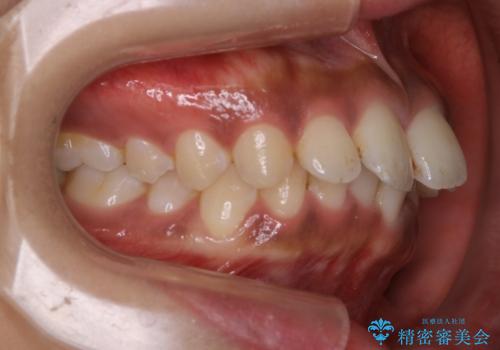

インビザライン矯正 歯を抜かずに出っ歯を改善!

- 出っ歯と前歯の隙間が空いていることを気にされて来院されました。

また、自然な感じで口元を下げていとのことでした。

奥歯のかみ合わせが問題なかったため、上顎の前歯の隙間を閉じるとともに、上顎の歯の側面を削ることをメインにして、出っ歯を改善する治療計画としました。

上顎の歯の傾きを変えるうえで、下顎の歯とのバランスのことも考え、下顎の歯の側面も削ることを加えています。

また、今回は口元を変えたい中に、劇的な変化は避けたいとのことだったので、抜歯をしない計画としています。

抜歯をしない場合、口元の変化は感じにくいですが、前歯の傾きが変わることで、口の閉じやすさは感じていただけたとのことです。

症例にもよりますが、本症例は奥歯のかみ合わせに問題がなかったので歯の側面を削ることメインに、前歯の傾きを改善することができました。

抜歯を行う場合や抜歯をしなくても奥歯の位置をずらす場合は、治療期間が長期化することが多いですが、今回は歯を削ることで改善できたため、短期間で治療を完了することができました。